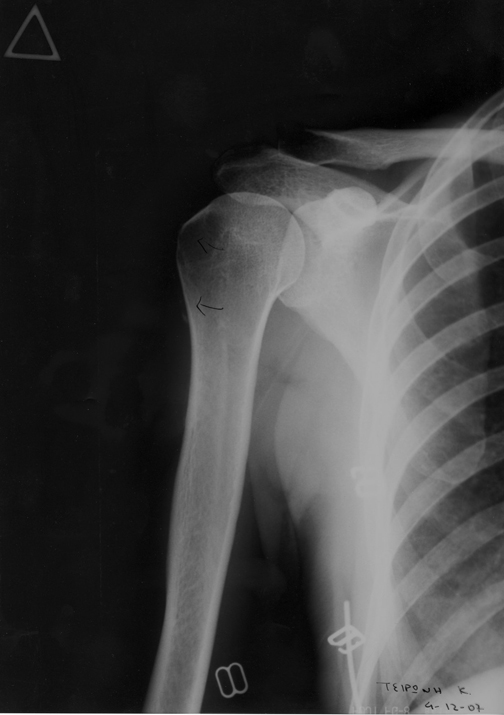

Μετά

Απεικόνιση τενοντίτιδας υπερακανθίου μετά τη θεραπεία:

Απεικόνιση τενοντίτιδας υπερακανθίου μετά τη θεραπεία